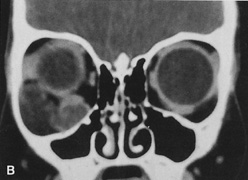

Fig. 25. A,B. Coronal (A) and axial (B) CT scans demonstrating well-encapsulated mass posteriorly in the superonasal orbit. An excellent alternative to transcranial orbitotomy for this lesion is an anterior approach via a vertical-lid splitting incision.